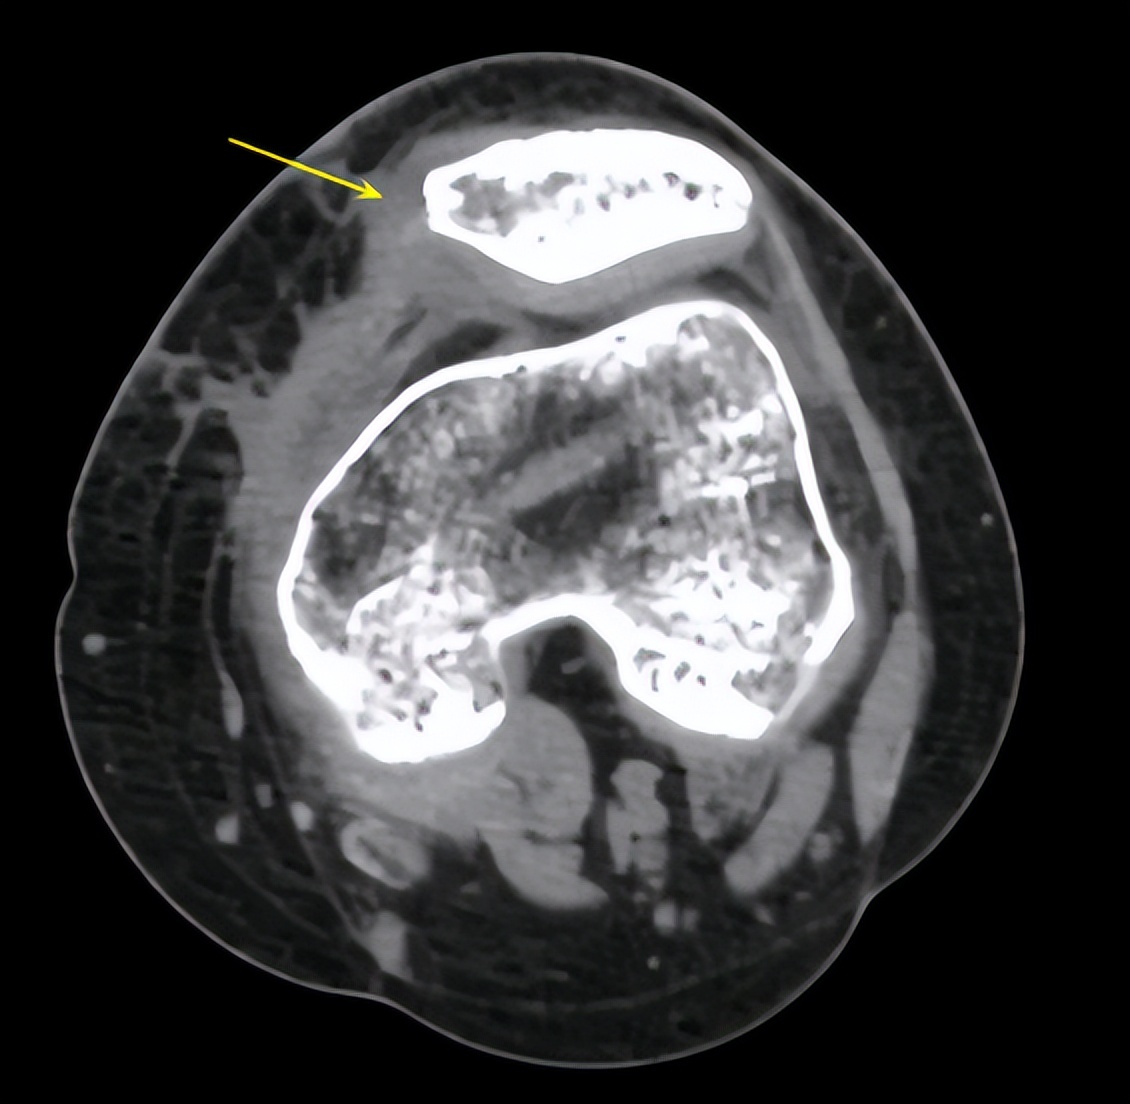

△术前脱位的髌骨(左图),髌股韧带重建后髌骨恢复正常位置(右图)

1

2

△术前可见髌股韧带断裂(左图),术后可见重建的韧带(右图)